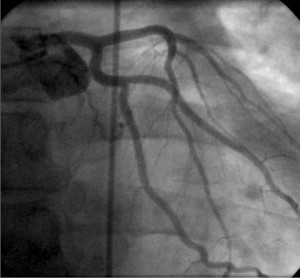

In order to analyze coronary flow as a continuous variable, the corrected TIMI frame count / Minim Luminal Diameter (CTFC/MLD) was chosen, and frame count was manually done through frame-by-frame count. The method proposed by Michael Gibson4 and improved by Goran Stankovic6 was adapted by counting the number of frames needed by the coronary flow to reach the standardized distal markers for the left anterior descending artery and for the right coronary artery, and the analysis of the longest dye path was chosen for the circumflex artery (Figures 1-6). The sizing of the minimal luminal diameter was done using the Quantitative Coronarography Analysis (QCA) method, using the software incorporated in angiography machines.

Figure 1. Example of analysis of a Left Anterior Descending artery Acute Coronary Syndrome: the white arrow shows the culprit lesion on the Circumflex artery and black arrows show the markers for flow analysis.

Figure 2. Example of analysis of a non-culprit Circumflex artery: the white arrow shows the culprit lesion on the Left Anterior Descending artery and black arrows show the markers for flow analysis.

Figure 3. Example of analysis of a non-culprit Right Coronary Artery: black arrows show the markers for flow analysis.